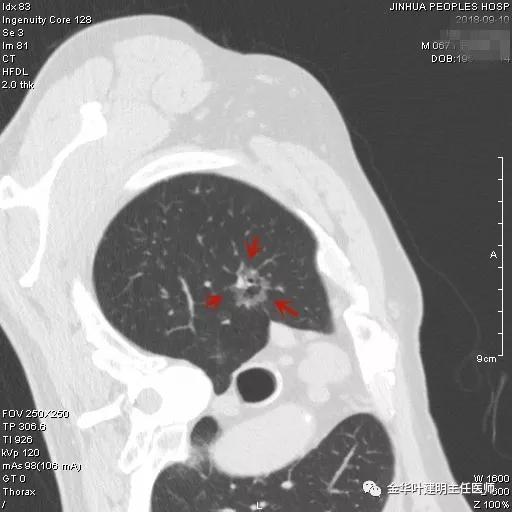

金华的阚某,今年67岁,前些日子因为“咳嗽、咳痰”到金华市人民医院就诊,因为考虑肺部感染,建议其住院抗炎治疗及进一步完善胸部CT等检查,结果示:右肺上叶磨玻璃结节,建议靶扫描及病理学检查;两肺多发感染性病变;左下支气管扩张等诸多肺部疾患。其CT检查影像如下:

上图示右上叶磨玻璃结节

阚某是本院一护士的亲戚,遂找到胸外科叶建明主任医师会诊阅片,考虑是不是肺癌,要不要手术及靶扫描,以及如果需要手术,何时为宜?叶建明仔细阅片并与谭海栋副主任医师商量后,认为其右上肺磨玻璃结节是较为典型的浸润性腺癌影像表现,且与正常肺组织之间并不是界限清楚的,而是呈浸润性改变,但实性成分目前仍不明显,考虑为浸润性腺癌贴壁生长型或腺泡型可能大,应该进一步完善胸部CT靶扫描,以观察病灶细节。手术是要做的,手术方式的确定等靶扫描之后再定。以下为靶扫描影像:

以上诸图示右上叶病灶,是典型的腺癌影像,直径约2.5厘米许